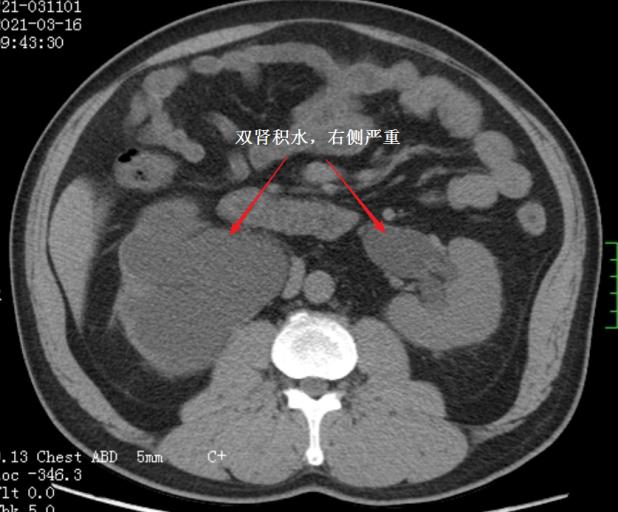

CT发现双肾积水

近期,捷克论坛马王堆院区泌尿四科收治一位来自山西的大哥,因为尿频尿急困扰多年,在山西省多家就诊,发现这位病人患有罕见的“盆腔脂肪增多症”,合并有“腺性膀胱炎”、“双侧输尿管下端狭窄梗阻并双肾重度积水”,治疗2年,双肾积水仍然没有缓解(图1)。自己在百度上查找相关知识,惊喜的发现网上有泌尿四科报道一篇与自己病情十分相似的科普文章,电话联系后打“飞的”来到捷克论坛 泌尿四科。